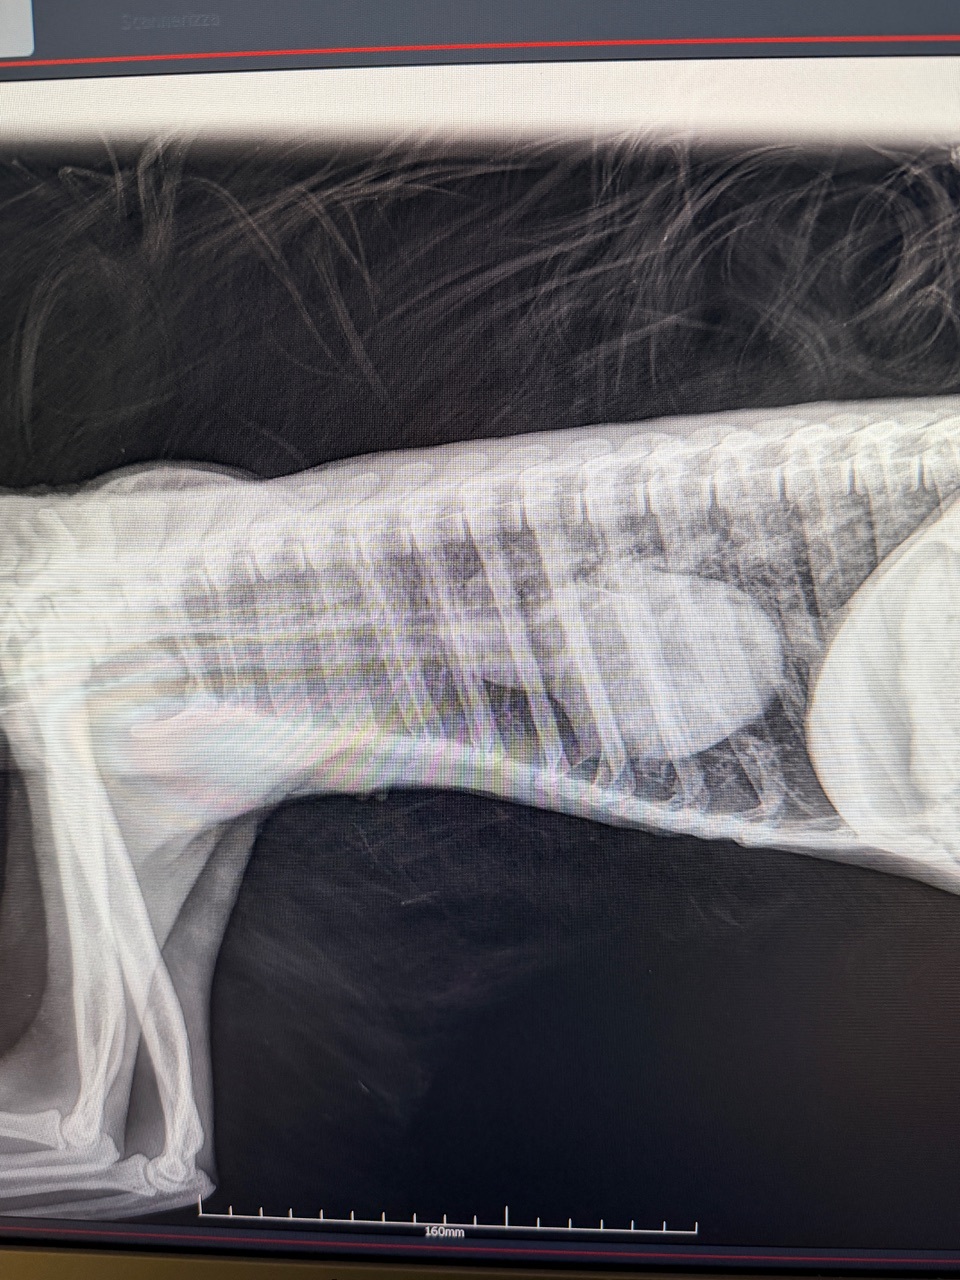

Un altro caso eccezionale ha visto protagonista una femmina di Bradipo didattico (Choloepus didactilus) di 8 anni, ospitata in un parco faunistico. La paziente è stata portata in clinica per sospetta polmonite, una condizione che richiedeva diagnostica avanzata e trattamenti non eseguibili in campo.

Grazie alla sedazione, il team ha potuto effettuare una visita approfondita, radiografie ed ecografia, confermando la diagnosi. Il bradipo è stato dimesso con una terapia mirata, nella speranza di un pieno recupero.

Nella foto: un estratto delle immagini di diagnostica effettuate